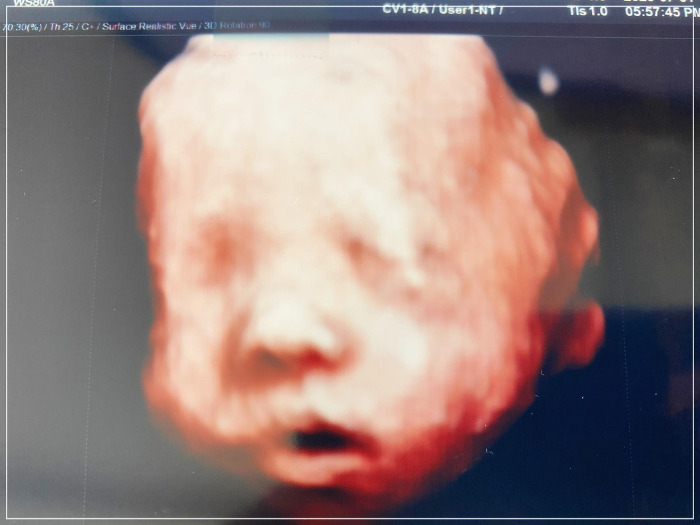

임신한 지 200일째 되는 날, 널 만나기 80일 전에 <입체 초음파>를 찍으러 갔어. 너의 얼굴을 자세히 볼 수 있단 기대감에 설레어서 전날 잠을 설쳤어. 20분 정도의 시간이었는데, 2분 같이 느껴지더라. 눈을 감고 있었는데 약간 처진 눈은 나를 닮은 거 같고, 코와 입 그리고 귀는 아빠를 닮았더라.